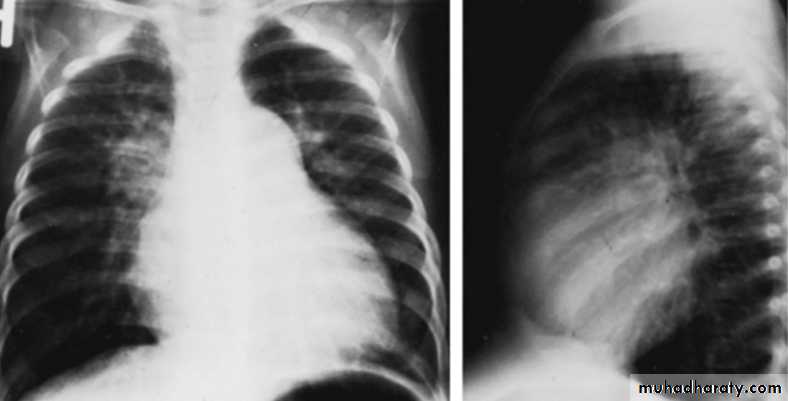

With large VSD cardiomegaly of varying degrees is present and involves the LA, left ventricle (LV), and sometimes RV. Pulmonary vascular markings increase. The degree of cardiomegaly and the increase in pulmonary vascular markings directly relate to the magnitude of the Lt to Rt shunt.

CXR of 6 years old child PA and lateral views showing cardiac enlargement and increased pulmonary markings